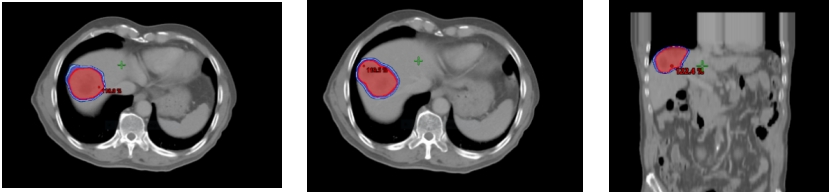

本次治疗为患者制定了科学的剂量方案:总剂量49Gy,分7次照射,单次剂量7Gy,在精准锁定肝内转移病灶的同时,最大程度减少对周围正常肝组织及邻近器官的损伤,实现“精准打击、高效杀伤”的治疗目标。

(▲放疗剂量图)